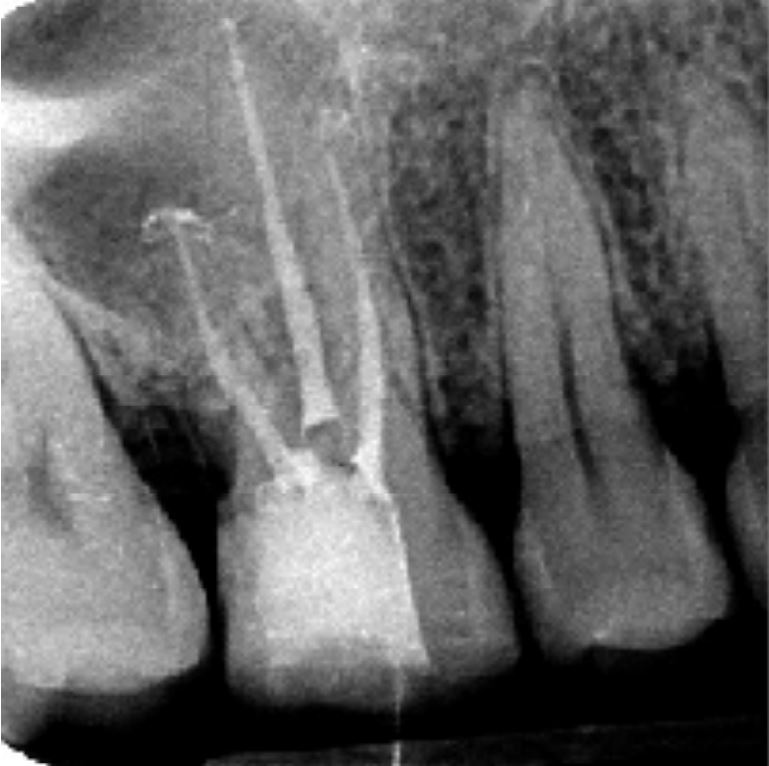

Radiografia postoperatoria

- Otturazione con guttaperca e cemento all'ossido di zinco-eugenolo

- Termocompattazione

- Restauro in composito a 2 superfici occluso-distale